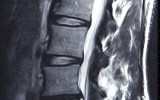

Scans for injured ankles and lower back pain are just some of the costly tests being overprescribed.